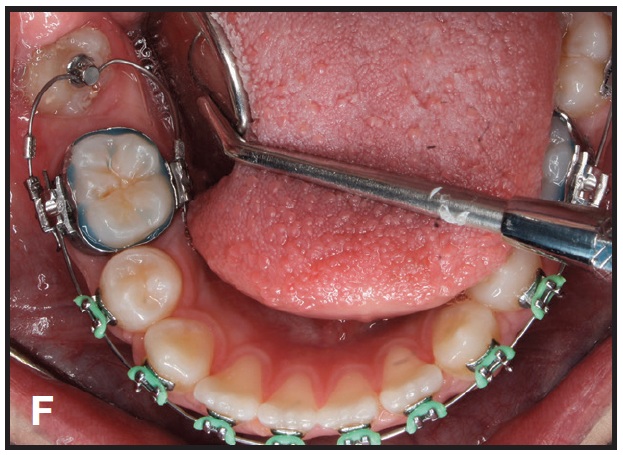

This technique is demonstrated in a 13-year-old female patient with an impacted lower right second molar (D). A U-loop spring was activated after surgical exposure of the tooth (E). Two months later, the second molar had been partially uprighted (F). After three more months of uprighting, the spring was removed and a continuous archwire was placed (G). It took another three months to completely upright the molar using straightwire mechanics, with no side effects on the anchor units (H).